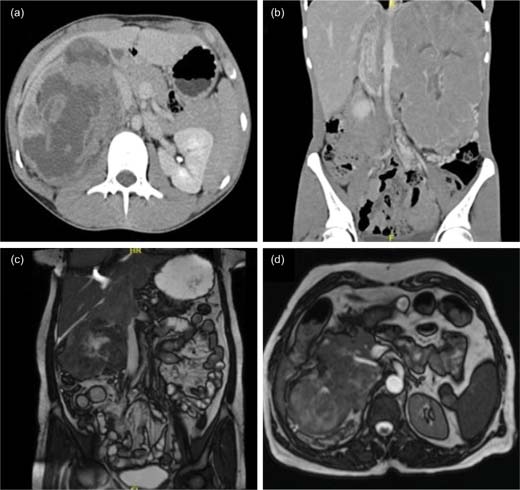

Three of the cases had nonspecific imaging findings and were thought to be Renal cell carcinoma (RCC) provisionally (Figures 1a, b, and c). In contrast, another patient was diagnosed with an upper tract transitional cell carcinoma (TCC). Magnetic resonance (MR) urography of this case (Figure 1d) showed a heterogenous well-defined mass lesion of 8 × 6-cm size predominantly iso-intense in T2 and iso to hypo-intense in T1 with restricted diffusion, involving renal pelvis of the right kidney and anteriorly compressing IVC with focal loss of the fat plane. Gross hydronephrosis was noted with thinning of parenchyma along with deranged renal parameters. All cases underwent radical nephrectomy and lymph node dissection. The median size of the tumor was 14 cm (range 12–25.5 cm). Two patients underwent IVC thrombectomy. One patient, diagnosed with intrapericardial IVC thrombus, required cardiopulmonary bypass but had significant intraoperative blood loss because of extensive neovascularization. She developed disseminated intravascular coagulation (DIC) postoperatively and succumbed to the disease.

Figure 1: (a) CECT abdomen and pelvis transverse section (Case 1) showing right renal mass, compressing medially the right renal vein, ureter, and IVC with sectoral contact of about 180° with no apparent tumor thrombosis. (b) CECT thorax and coronal abdomen section (Case 2) revealed that left renal mass lesion with enhancing tumor thrombus extending up to the supradiaphragmatic IVC. (c) Plain MRI abdomen coronal section (Case 3) showing well-defined lobulated mass lesion with IVC thrombosis extending into the suprarenal IVC, below the diaphragm. (d) MR urography transverse section (Case 4) showing a well-defined mass of size 8 × 6 cm involving the renal pelvis, compressing IVC anteriorly. IVC, inferior vena cava; CECT, contrast-enhanced computed tomography.